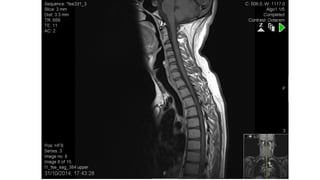

Spinal Lesions

cord lesion